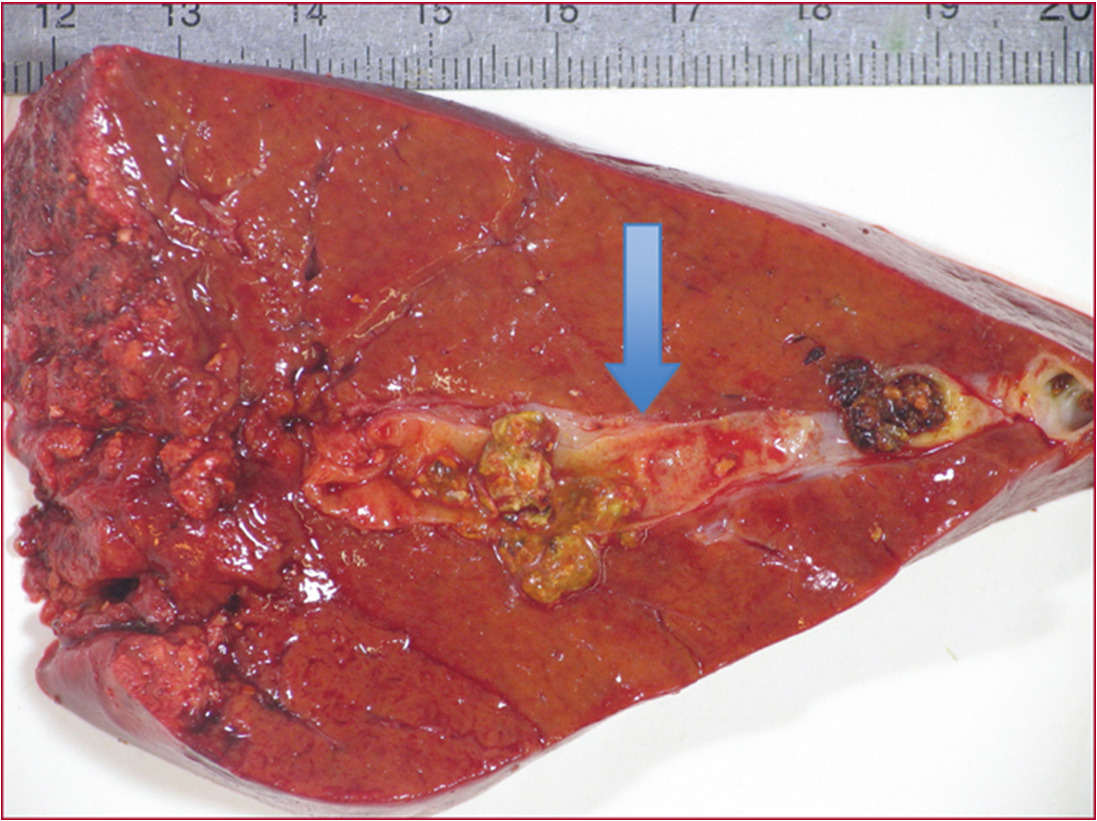

La cholécystectomie doit être évitée dans la mesure du possible car elle ne prévient pas le risque de récidive d’événement biliaire, qui est lié, dans la très grande majorité des cas, à la lithiase intrahépatique et non à la lithiase vésiculaire. La lithiase vésiculaire n’est présente que dans 30 % des cas de syndrome LPAC. En revanche, en cas de cholécystite aiguë lithiasique avérée, la cholécystectomie doit bien sûr être réalisée afin de limiter le risque de complications (perforation, abcès, péritonite). Une hépatectomie partielle peut être proposée en cas d’empierrement des voies biliaires intra­hépatiques, symptomatique ou compliqué (angiocholites, abcès) et en cas d’échec du traitement par AUDC, si cet empierrement est limité à un lobe ou à un segment du foie (fig. 3).